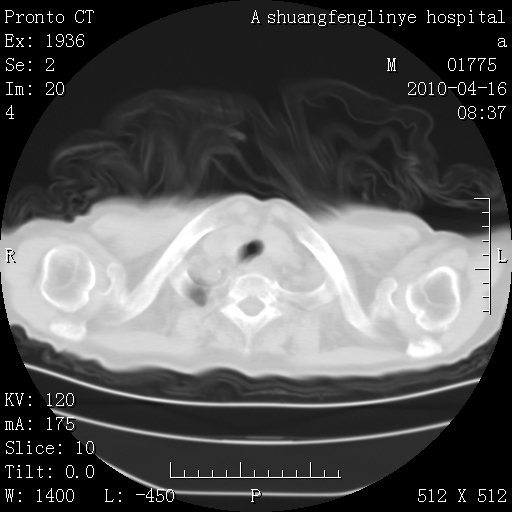

标题: CT25784:咳痰、请会诊!结核? [打印本页]

标题: CT25784:咳痰、请会诊!结核?

考虑左肺上叶增殖灶、纤维灶。

慢支肺气肿,左上陈旧性结核,主动脉冠脉钙化

1)左肺上叶结核(纤维、增殖病灶)。2)冠状动脉及主动脉钙化。